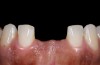

The pretreatment situation.

Figure 1

Figure 13